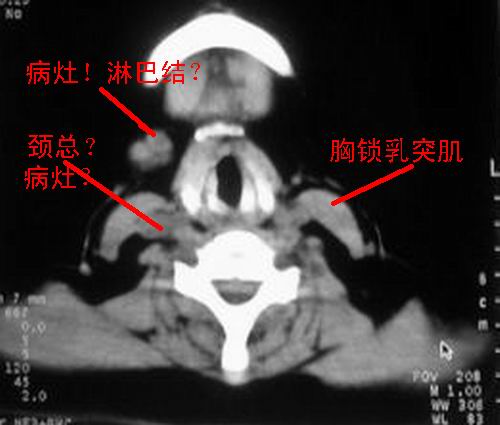

右侧胸锁乳突肌后方软组织密度肿块,界限清楚。多考虑:血管源性肿瘤!

就是,我说怎么变成胸锁乳突肌后方了,晕死啊!不知道后面跟风的战友看清楚图象没?

右侧胸锁乳突肌内侧略低密度结节,应该是静内静脉而不是淋巴结。

至于右侧颌下间隙的结节影,如果不考虑病史的话,可以诊断为淋巴结转移。但是结合病史“右侧颌下肿物3年”,又不象淋巴结转移了。建议ct增强扫描明确结节与右侧颌下腺的关系,或者穿刺活检定性。